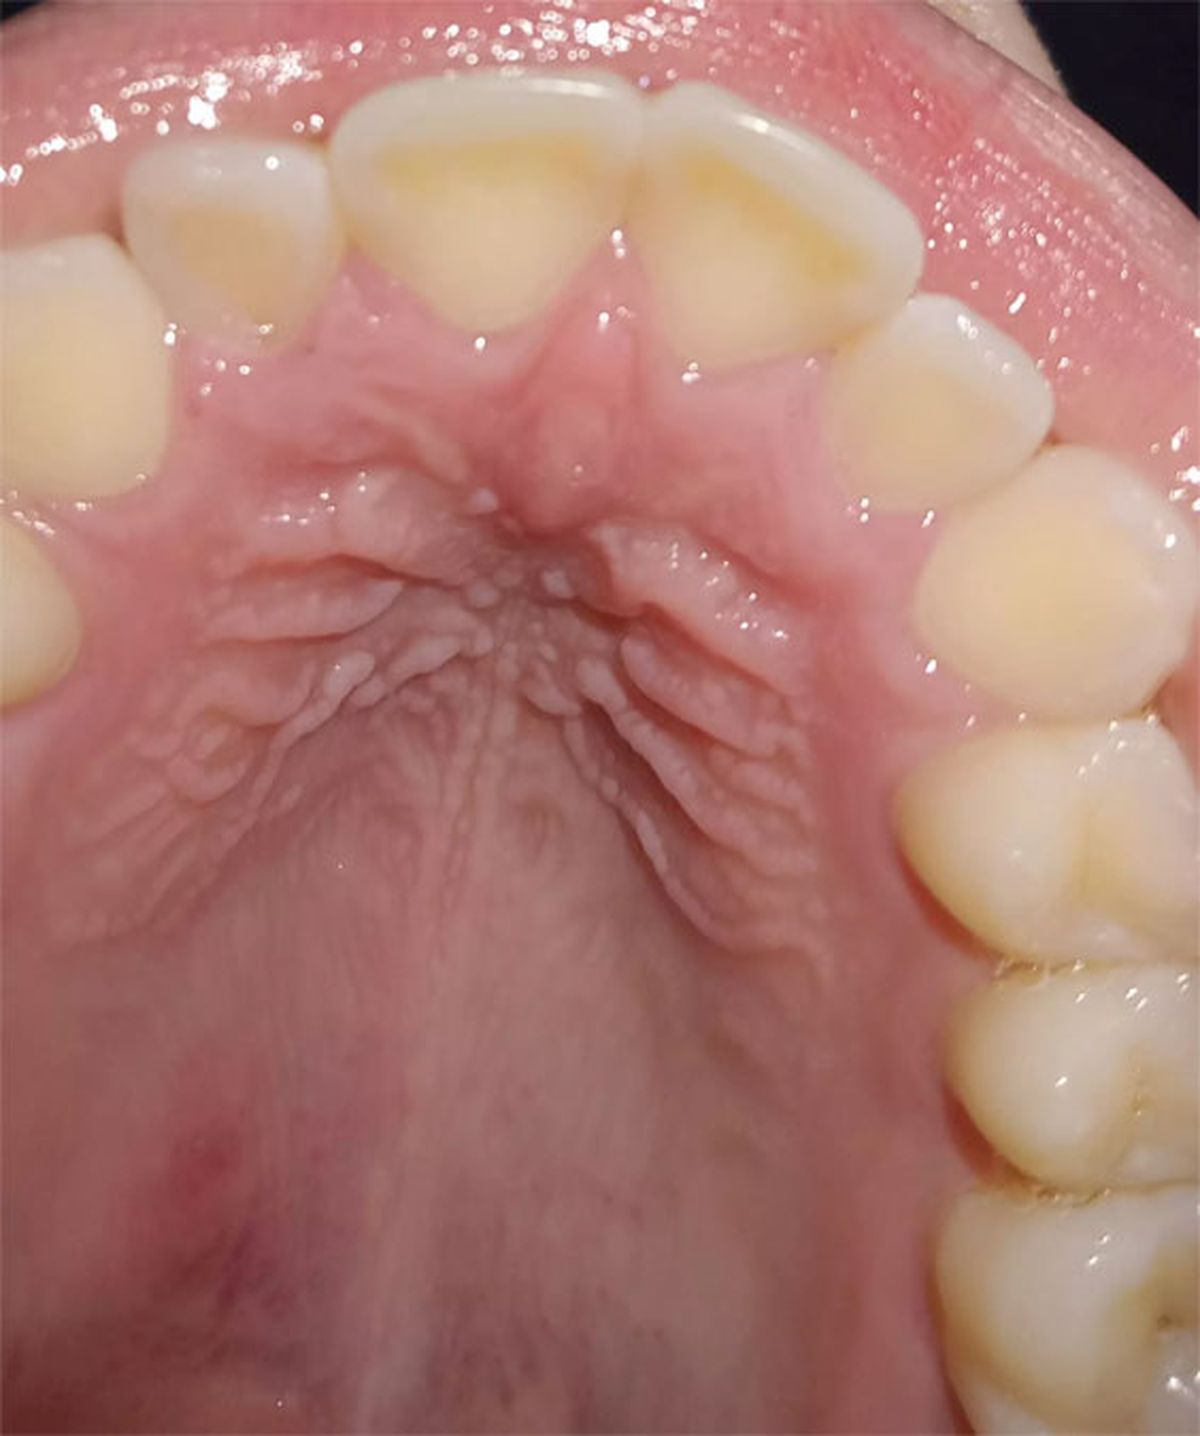

Desde la Clinica Dental Gross, de Málaga, España, aseguran que un paladar sano presenta un aspecto rosado, de color uniforme. Además, señalan que el cambio de tonalidad del paladar, a un color más amarillento, blanco o rojo vivo, es una señal de alerta.

Un paladar inflamado es una cuando el tejido de la parte superior de la boca, el piso de la nariz, se hincha por diferentes motivos.

Entre todos los síntomas que podrían señalar que un paladar está inflamado, se destaca:

- Dolor en el paladar

- Enrojecimiento e hinchazón

- Aparición de llagas

- Problemas para tragar alimentos

- Sensación de ardor o picazón

- Mal aliento